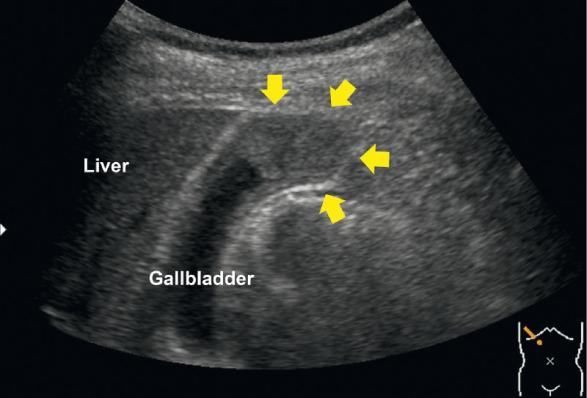

Fig. 1 Abdominal ultrasonography of gallbladder cancer, showing a protruded lesion (yellow arrowheads) at the gallbladder fundus

图1. 胆囊癌的腹部超声图像,显示胆囊底有一个突出病变(黄色箭头)。

A 79-year-old man presented to our hospital with a gallbladder tumor diagnosed using abdominal ultrasonography (AUS). AUS, contrast-enhanced computed tomography, and magnetic resonance imaging showed a protruded lesion at the gallbladder fundus (Fig. 1, Fig. 2). Endoscopic retrograde cholangiography (ERC) was performed, and cholecystography revealed a contrast agent defect at the gallbladder fundus (Fig. 3).

患者,男,79岁,入院后通过腹部超声检查(AUS)诊断出患有胆囊肿瘤。AUS、对比增强计算机断层扫描和磁共振成像显示,胆囊底部有一个突出病变(图1、图2)。进行了经内镜逆行性胆管造影(ERC),且胆囊造影显示,胆囊底部造影剂充盈缺损(图3)。